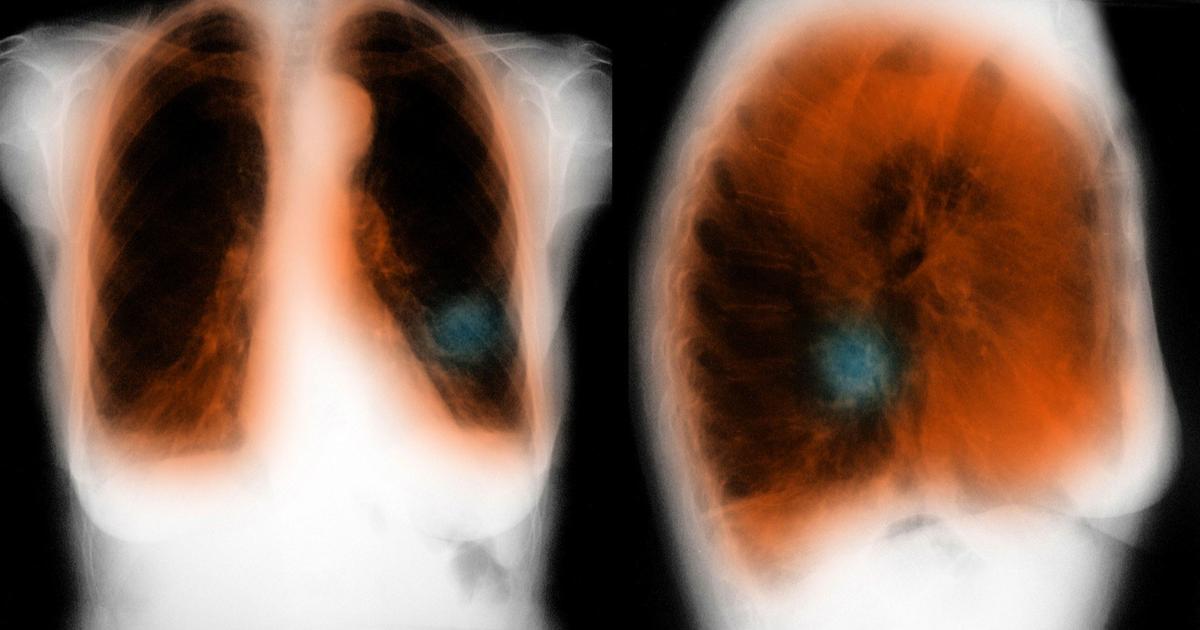

Здоровый образ жизни: Влияние курения